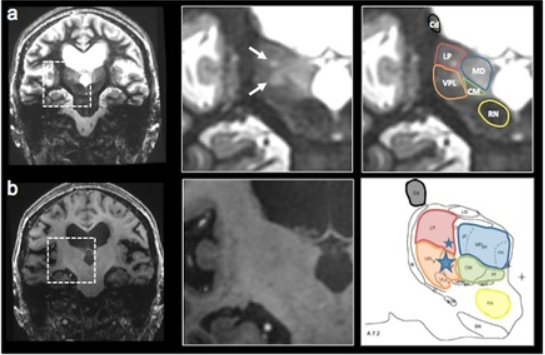

Thalamic nuclei are almost invisible on standard T1 and T2 MRI. We have been pioneering novel methods for visualizing thalamic nuclei. These are critical for many applications like deep brain stimulation (DBS) electrode placement and focused ultrasound ablation of thalamic nuclei for treatment of essential tremor. They are also important to study atrophy of these nuclei in various neurodegenerative and neuro-psychiatric disorders. We have developed and optimized a novel white-matter-nulled (WMn) MRI sequence which enables clearer delineation of thalamic nuclei (top left, top centre) compared to conventional T1 MP-RAGE sequence (bottom left, bottom centre). Manual segmentation of some thalamic nuclei and the Morel atlas are shown in the far right column.